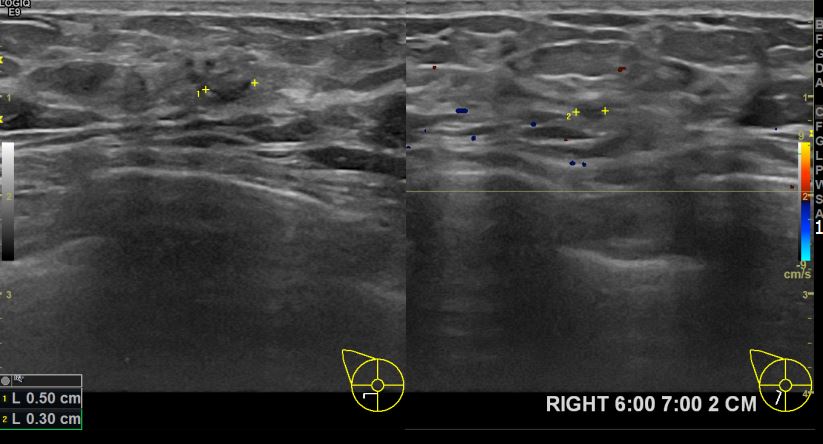

아산유외과개원후 644번째 유방암진단

상기환자 외부검사상 이상소견으로 내원하신 60대여성으로 우측유방의 의심스러혹

조직검사시행해 유방암 진단되었습니다.